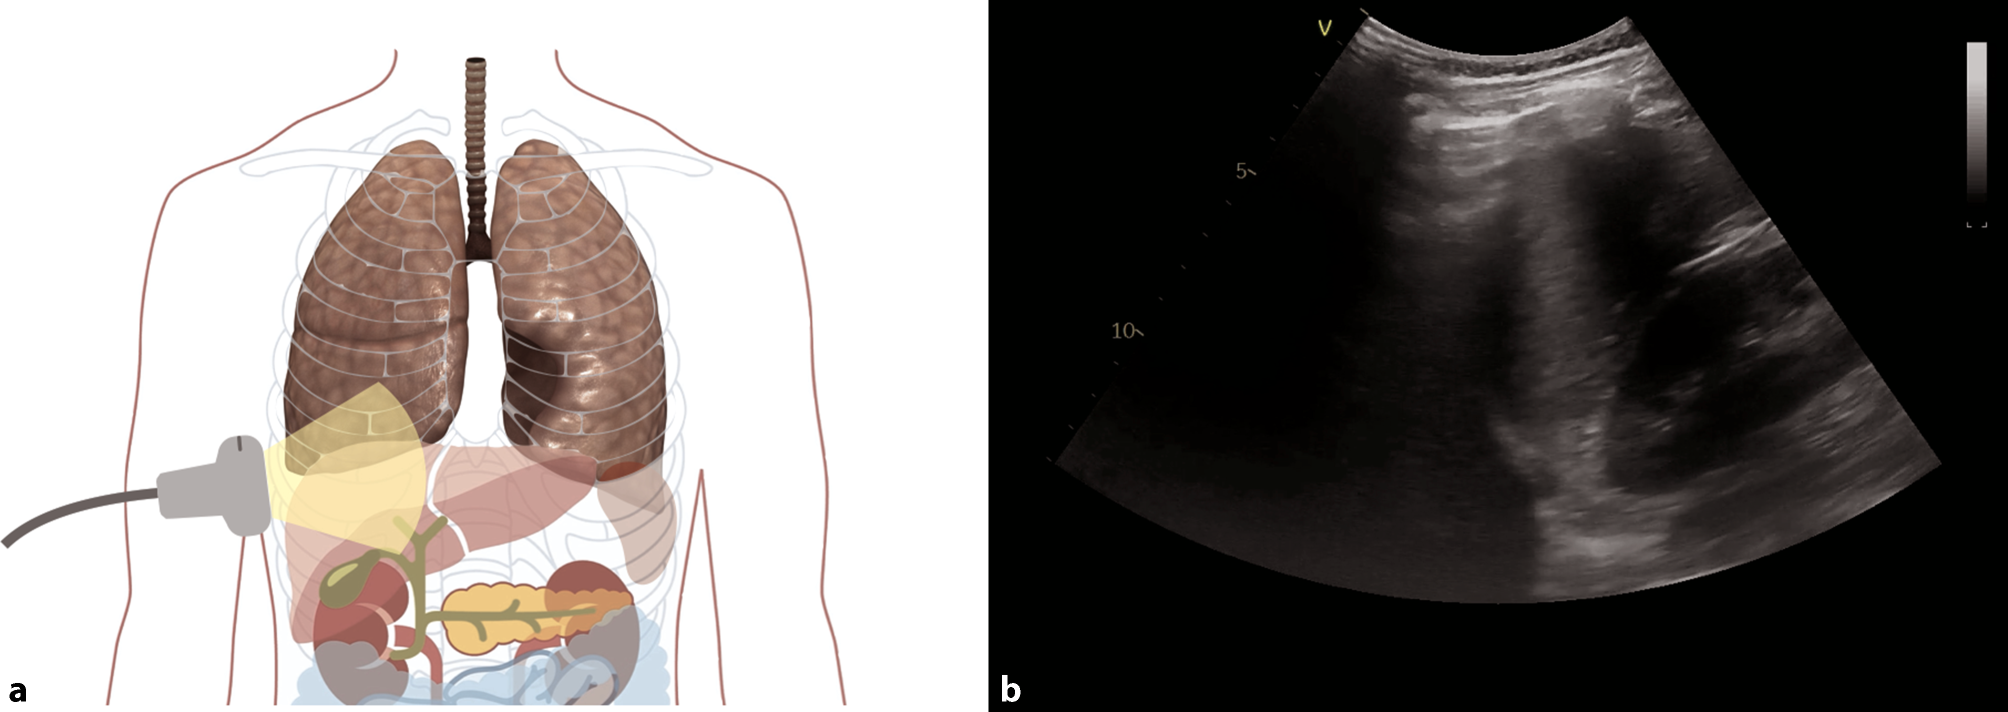

Fig. 7

Anatomy and sonoanatomy of the lung. a Anatomy of the lung in a longitudinal view. b Normal sonographic anatomy in a patient after a severe COVID-19 infection

As COVID-19 pneumonia is characterized by a patchy distribution of affected lung parenchyma, areas with a normal appearance in LUS are seen next to pathological areas (Figs. 5a, 6 and 7; [24]). Due to the patchy distribution, a thorough examination is recommended, yet there is no validated scanning scheme [23]. We recommend a 12-zone scanning protocol, as it is, in our experience, simple to apply, reproducible, and easy to learn (Fig. 8). Beginning with zone one with a longitudinal view, followed by a transverse view, a scan of all intercostal spaces should be performed. Whenever possible, scanning of the posterior regions should be included for patients in a supine position, although this may not always be feasible. In this case, it is recommended to consider scanning the posterior regions during prone positioning [23].